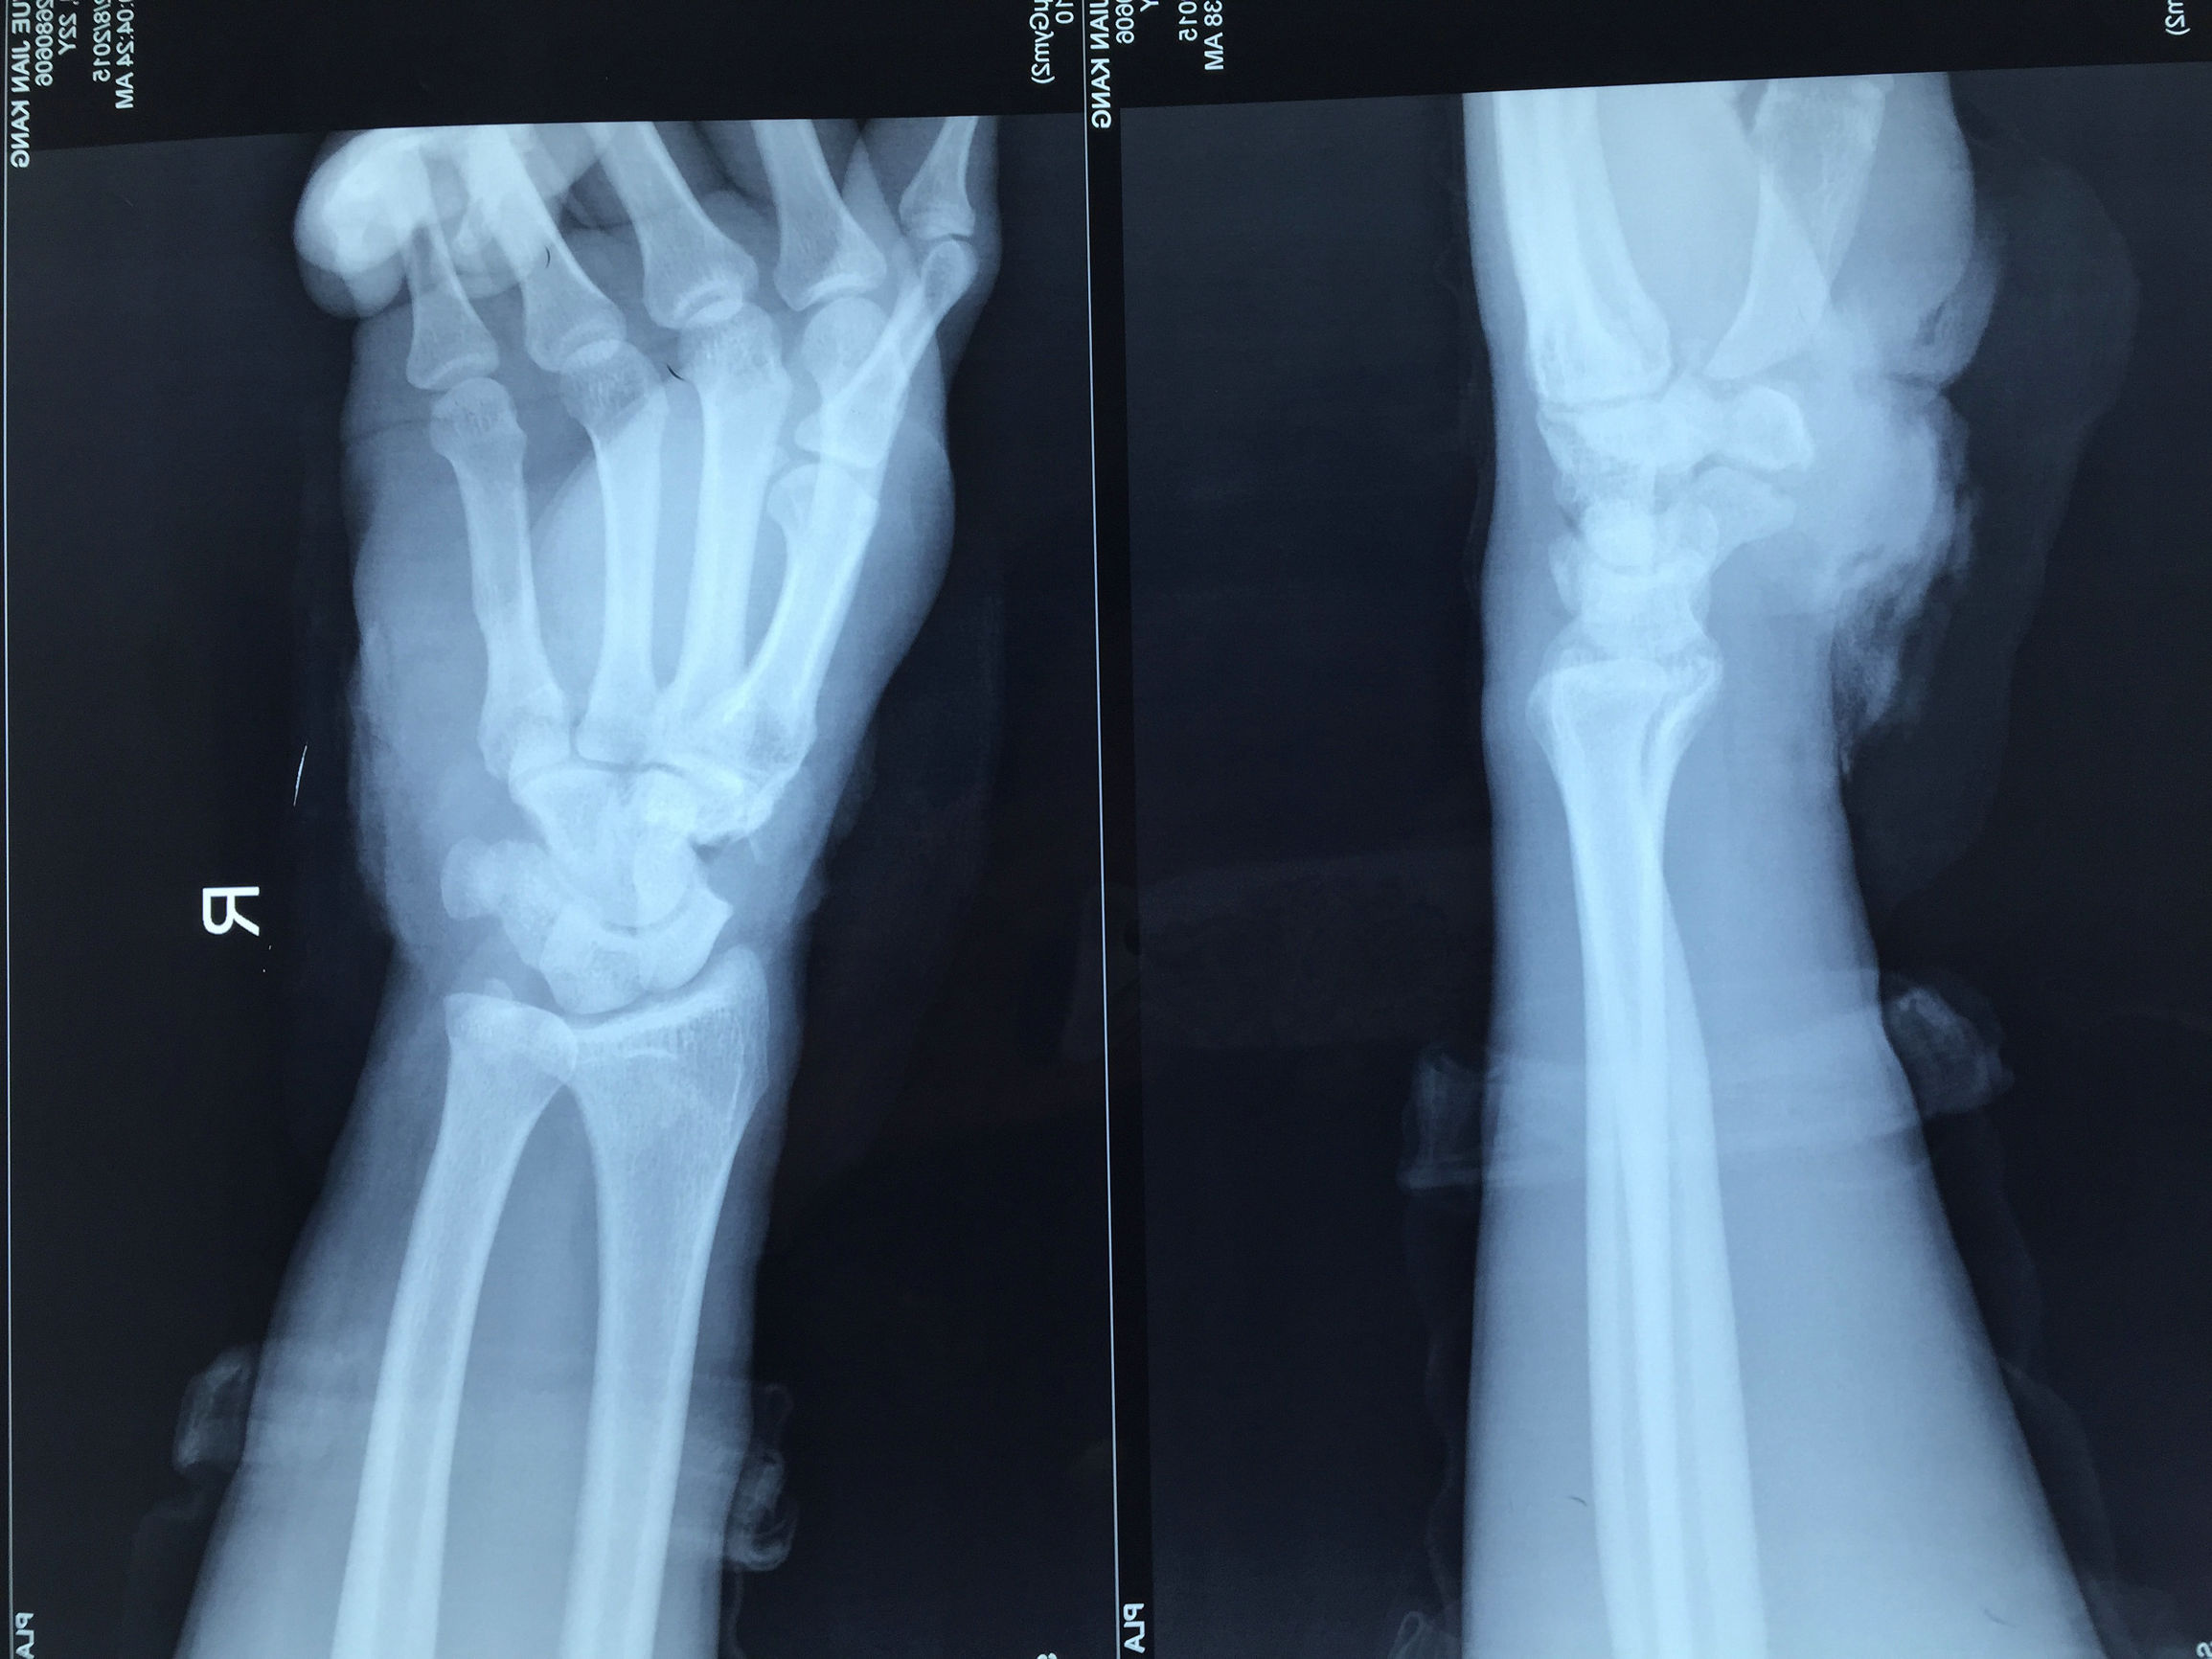

2015年12月8日,306医院创伤骨科收治了1位电锯损伤右手的青年小伙,是典型的割伤、绞伤、烧伤(电锯高温)集一体的手外伤。患者右手被电锯割伤,导致右腕桡动脉断裂;右腕正中神经、尺神经断裂;右腕部肌腱损伤;右腕第一腕掌关节开放性脱位骨折。骨科创伤团队急诊为患者实施了脱位复位、骨折固定、精细修复断裂的肌腱,在显微镜下无创吻合断裂的神经、血管。术中确保吻合口通畅、神经断端精细修复,术后采用屈碗、屈指位石膏托固定。为避免肌腱的粘连,我们采用支具保护装置,早期进行肌腱被动锻炼,目前患者已出院,创面恢复良好,手指末梢血运正常。

手术前 X 片(腕掌关节开放性脱位骨折)